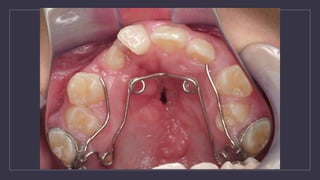

Orthodontic Treatment ofTransitional Dentition • The purpose the dentition adjacent to cleft has to be orthodontically repositioned to prepare the cleft side for the secondary alveolar bone graft • Preparing the maxillary arch for a bone graft (6-12 months) : 1. Bonded edgewise appliance 2. Supported with a maxillary expander quad helix expander

Quadhelix to expandprior to ABG

angle brackets tokeep roots away from cleft